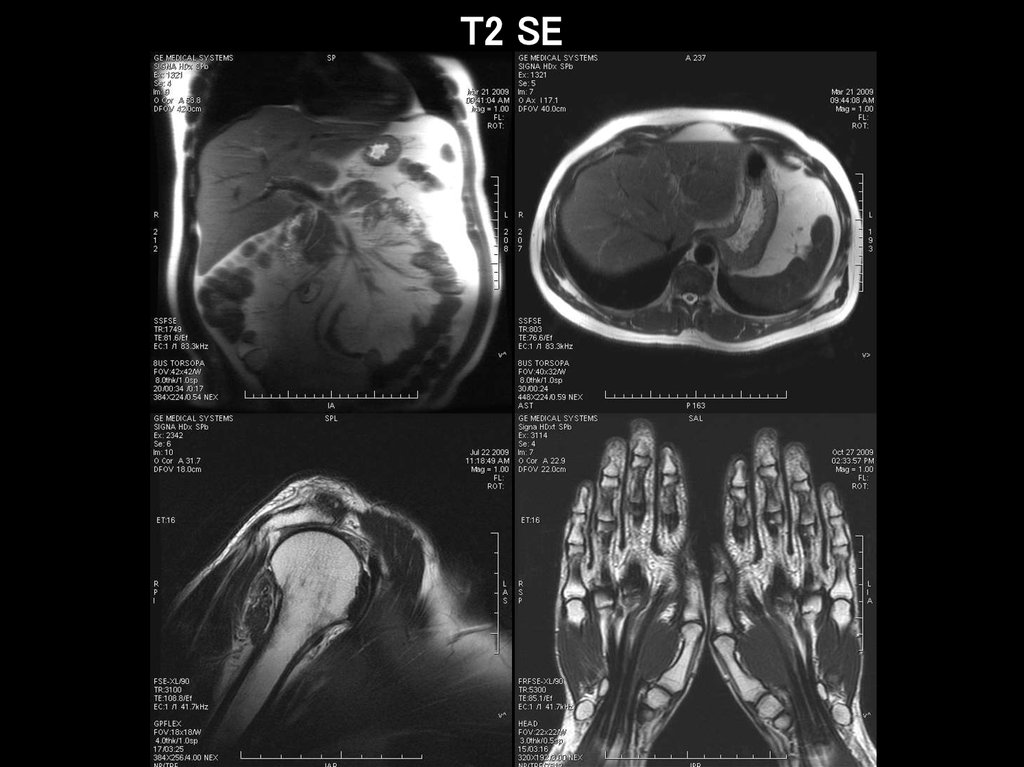

T2 SE